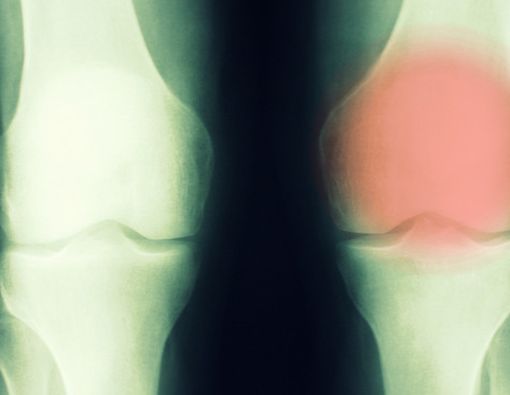

Bengkak pada area yang terasa nyeri

Beberapa minggu setelah awal kemunculan nyeri tulang, selanjutnya dapat muncul keluhan bengkak pada area yang sudah terasa nyeri sebelumnya. Mungkin juga benjolan juga terlihat pada area tersebut.

Keluhan ini dapat disertai tanda peradangan, misalnya saja timbul kemerahan pada area yang bengkak dan terdapat benjolan. Apabila gejala tersebut muncul di area sendi, bisa lebih bahaya lagi. Sebab, kondisi tersebut dapat menyebabkan penderita kesulitan untuk menggerakkan sendi, sehingga sulit untuk bergerak apalagi beraktivitas.